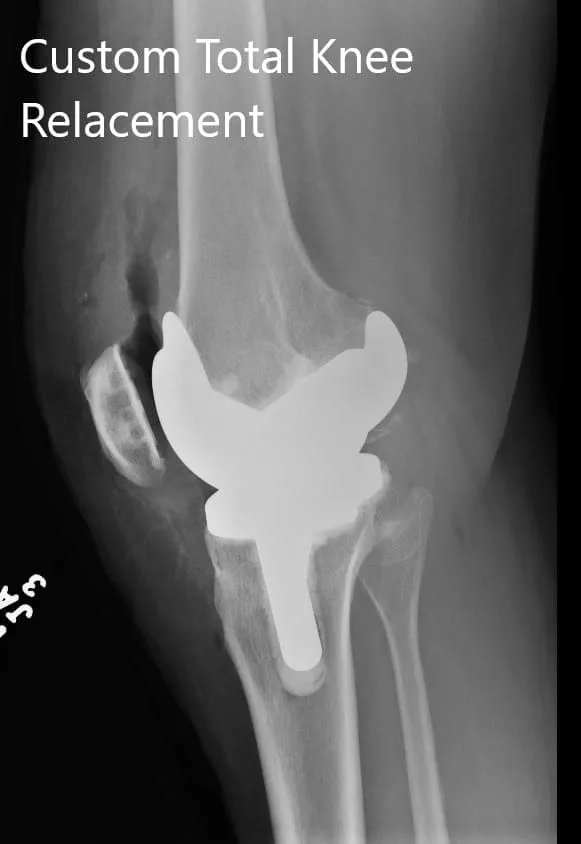

Imágenes postoperatorias que muestran vistas AP y oblicuas de la rodilla derecha.